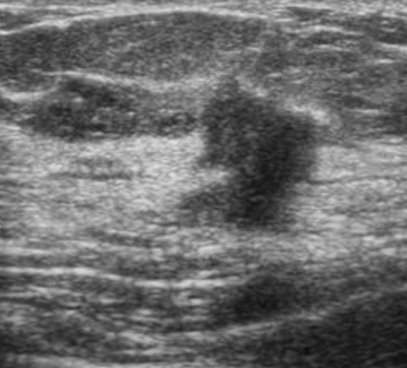

Признаки рака молочной железы на УЗИ

Однако при наследственном раке молочной железы чаще отмечается регресс (обратное развитие) или уменьшение размеров образования на фоне химиотерапии, проводимой до операции, что можно увидеть на маммографии и/или УЗИ.